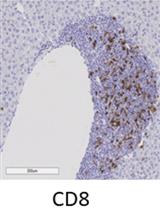

Immunostaining positive cells can be quantitated using free ImageJ. With this protocol, CD8α-positive cells are primarily found in the interstitium of the kidney. The potential backgrounds and no-specific bindings are minimal. eNOS-/- db/db mice spontaneously develop diabetic nephropathy at 8 weeks of age. These mice were treated with erlotinib (an epidermal growth factor tyrosine kinase inhibitor) or vehicle (water) from 8 to 20 weeks of age. Six photos from each mouse are taken, and the average is used as CD8α-positive cell density form one mouse. The number of CD8a-positive cells in the kidneys is quantitated from 4 mice from vehicle treated eNOS-/- db/db mice and erlotinib treated eNOS-/- db/db mice (Figure 1).

Figure 1. Inhibition of EGFR activity with erlotinib decreased renal CD8α lymphocyte infiltration in eNOS-/- db/db mice. A. The representative pictures of CD8a staining in the mouse kidneys from eNOS-/- db/db mice with vehicle or erlotinib treatment. B. Quantitative data (n = 4, P < 0.001). The value are presented as means ± S.D. The statistical analysis was performed using student’s t-test.